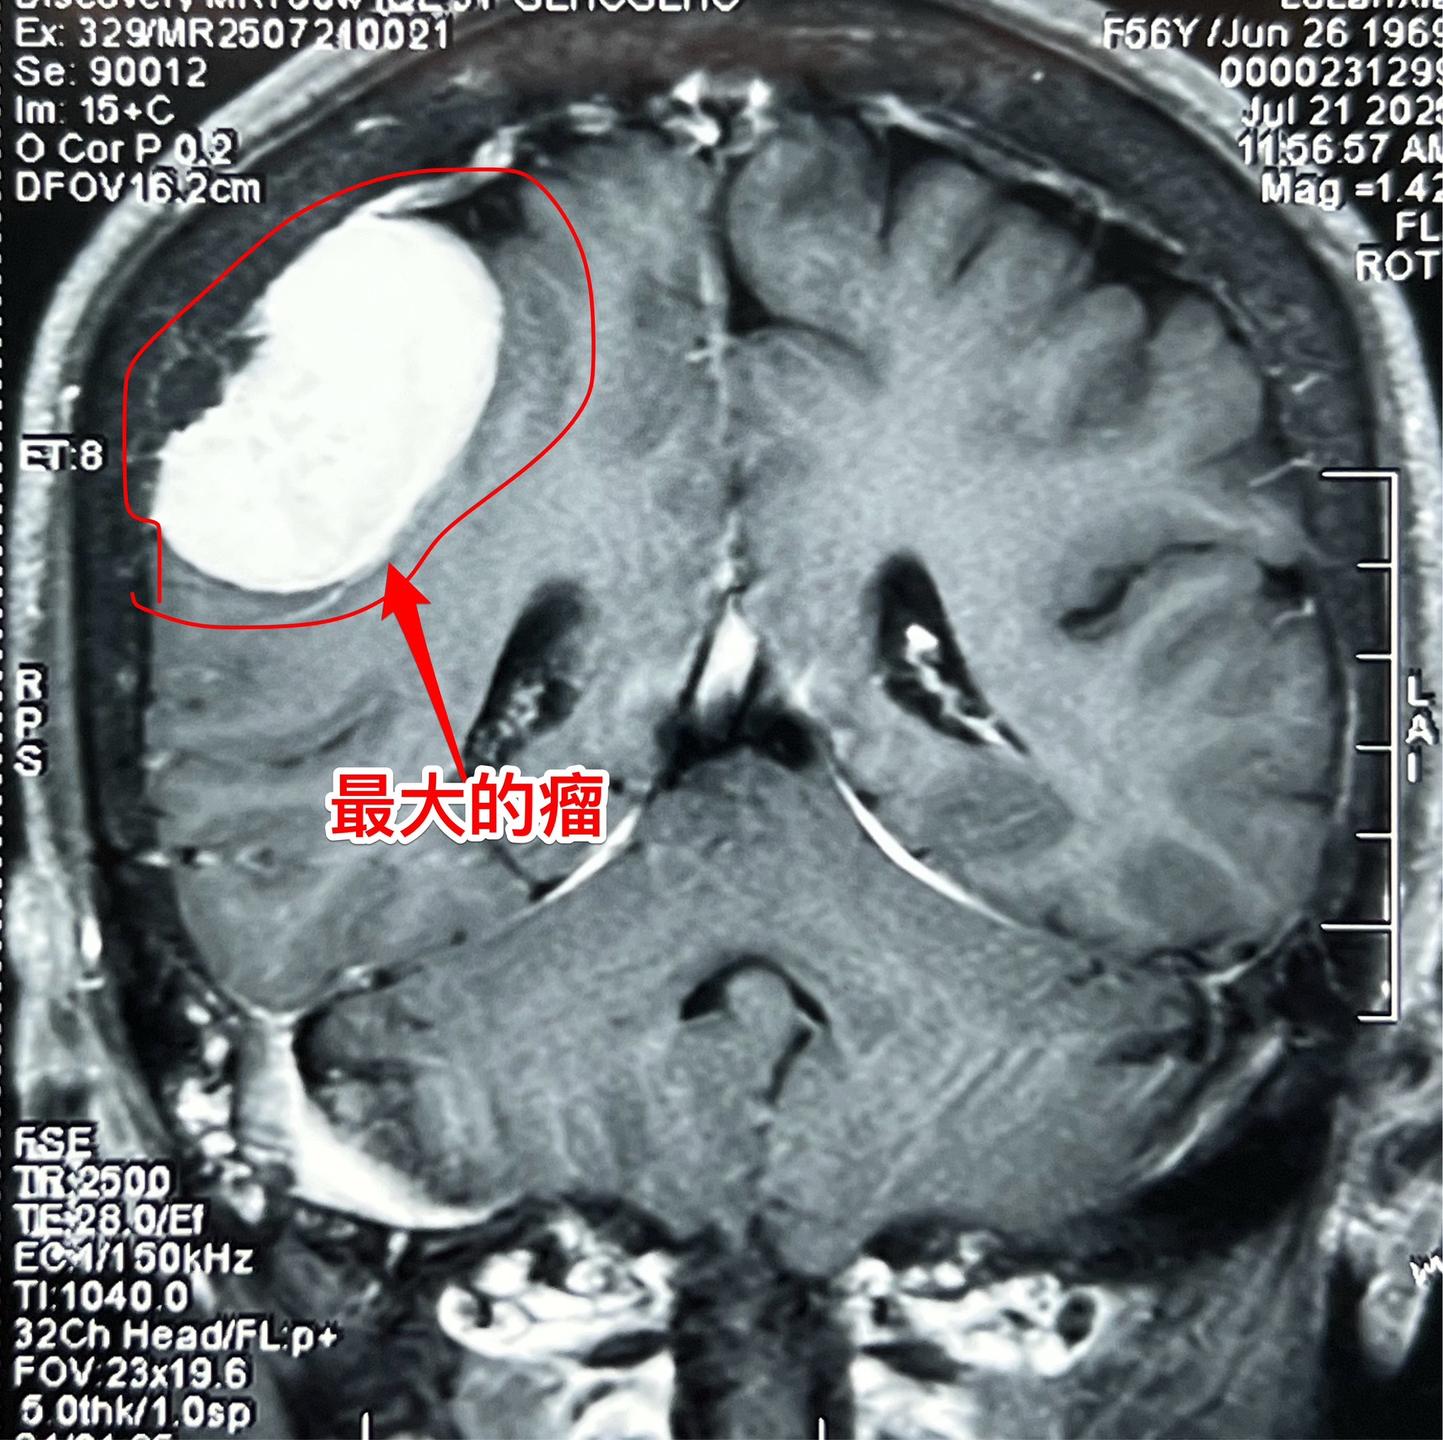

因头痛检查发现脑部有三个瘤。56岁女性,黄梅县人。平时身体很好,因路滑摔倒,检查发现脑部有三个瘤,最大的一个约5厘米。 患者的一个弟弟也是医生,推荐来找我作手术。 如图所示,经过详细的检查,确认第一个、第二个瘤是脑膜瘤,第三个瘤位于垂体窝内,考虑是垂体瘤。 今日(2025年8月3日)作手术,切除了两个脑膜瘤。垂体瘤暂时予以观察。